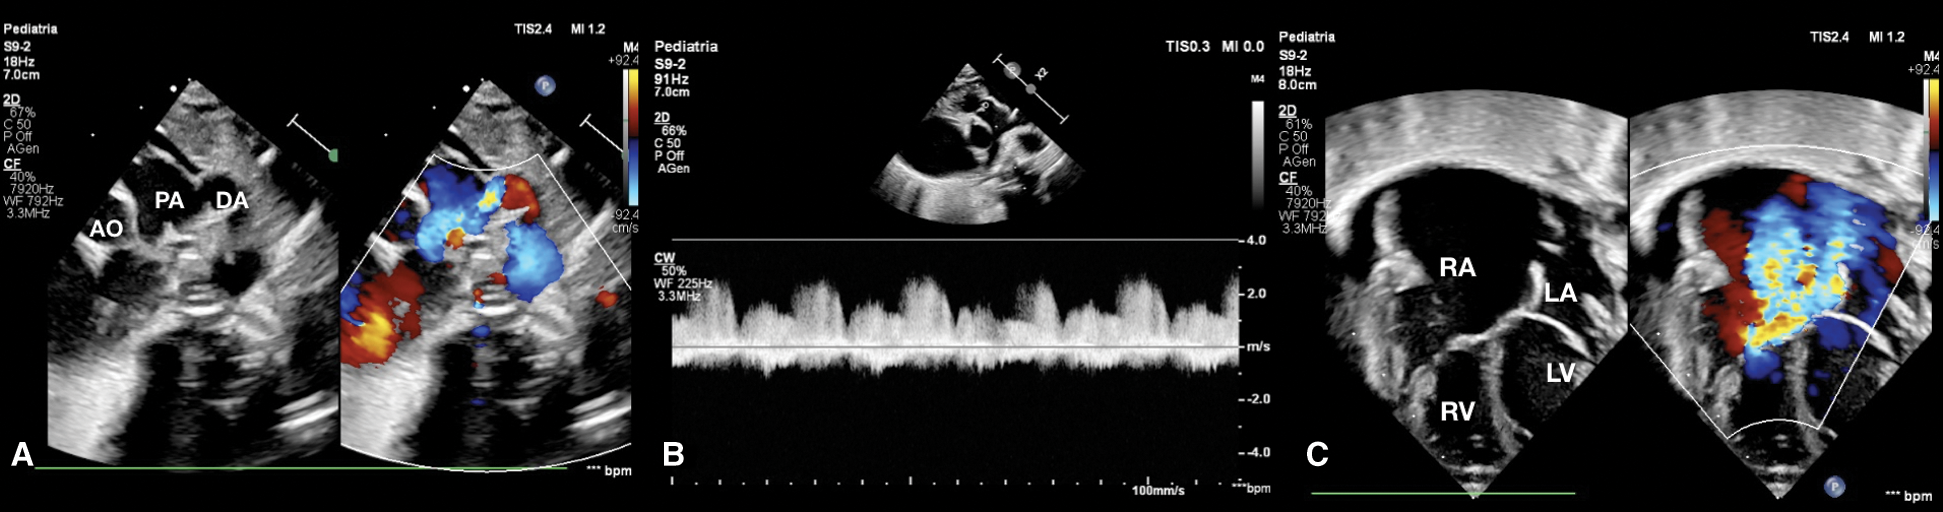

Echocardiography evaluation revealed tricuspid valve dysplasia with severe regurgitation and functional pulmonary valve atresia with intact ventricular septum. The massive tricuspid regurgitation was associated with enlarged right atrium (RA) (Fig. 1), without anterograde flow from right ventricle (RV) to pulmonary valve, resulting in a functional PA with reversal flow in the large patent ductus arteriosus (PDA) (Fig. 2) and pericardial effusion.

Figure 2: (A) Short axis parasternal view shows patent ductus arteriosus with reversal flow. (B) CW Doppler in pulmonary artery shows absence of anterograde flow. (C) Four-chamber view at birth shows severe tricuspid regurgitation, normal AV valves implantation, huge right atrium, pericardial effusion and normal size of right ventricle and left ventricle. AO aorta, DA ductus arteriosus, LA left atrium, LV left ventricle, PA pulmonary artery, RA right atrium, RV right ventricle

The distinguishing pathognomonic feature between Ebstein’s malformation and tricuspid dysplasia is the displacement and rotation of the hinge points of the tricuspid valvar leaflets, which is well differentiated with two-dimensional echocardiography providing some basic anatomical insights, and even more with three-dimensional imaging which is rapidly emerging as an important new clinical tool in congenital heart disease [3]. In our case two-dimensional echocardiography allowed to exclude Ebstein’s malformation showing clearly the right closing in trifoliate fashion of the leaflets of the tricuspid valve, hinged at the right atrioventricular junction (Figs. 1B, 1C and 2C).